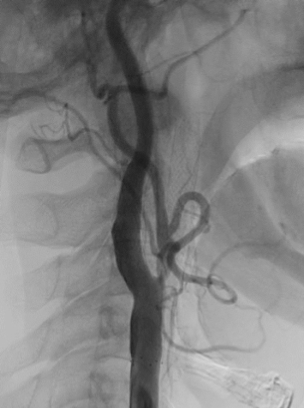

頚動脈ステント留置術

局所麻酔で手術を行います。足の付け根の動脈(大腿動脈)からカテーテルを挿入し,フィルターあるいはバルーン等で術中に血栓などが飛ばないように保護しながら(図4)、バルーンカテーテルで狭窄部を広げ(図5)ステントを留置(図6)し,血流の改善をはかります。当院では積極的に頚動脈ステント留置術を第一選択として治療を行っております。

頚動脈高度狭窄

術前の頚動脈造影写真です。〇内に頚動脈狭窄が見られます。

造影されていない部分にはプラークが付着しています。

頚動脈ステント留置術後の造影写真です。狭窄は改善しています。